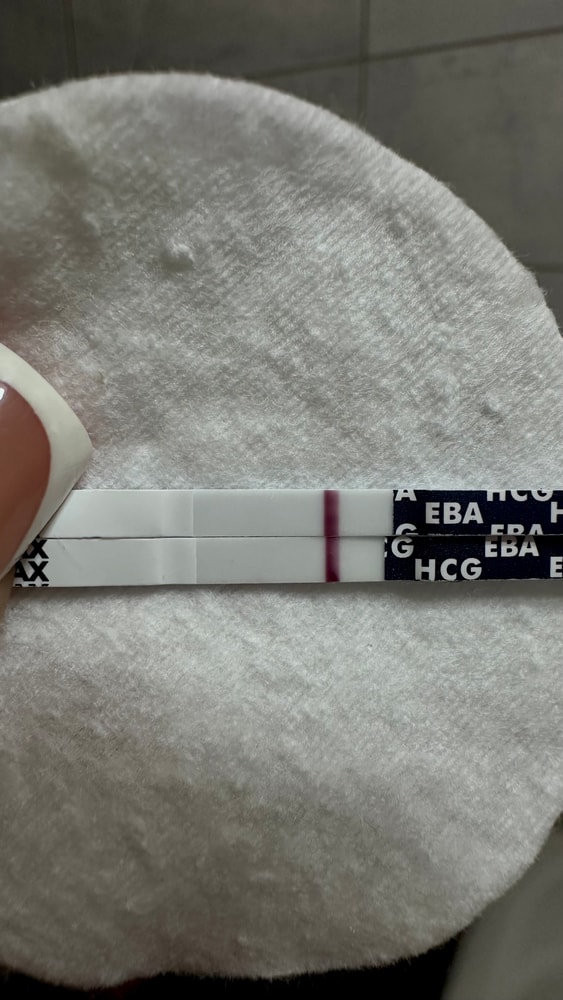

Писала сегодня пост с тенью на ЕВА

Писала сегодня пост с тенью на ЕВА

Тесты в студию🤗

Вот и мне отреагентили эти прекрасные тесты.